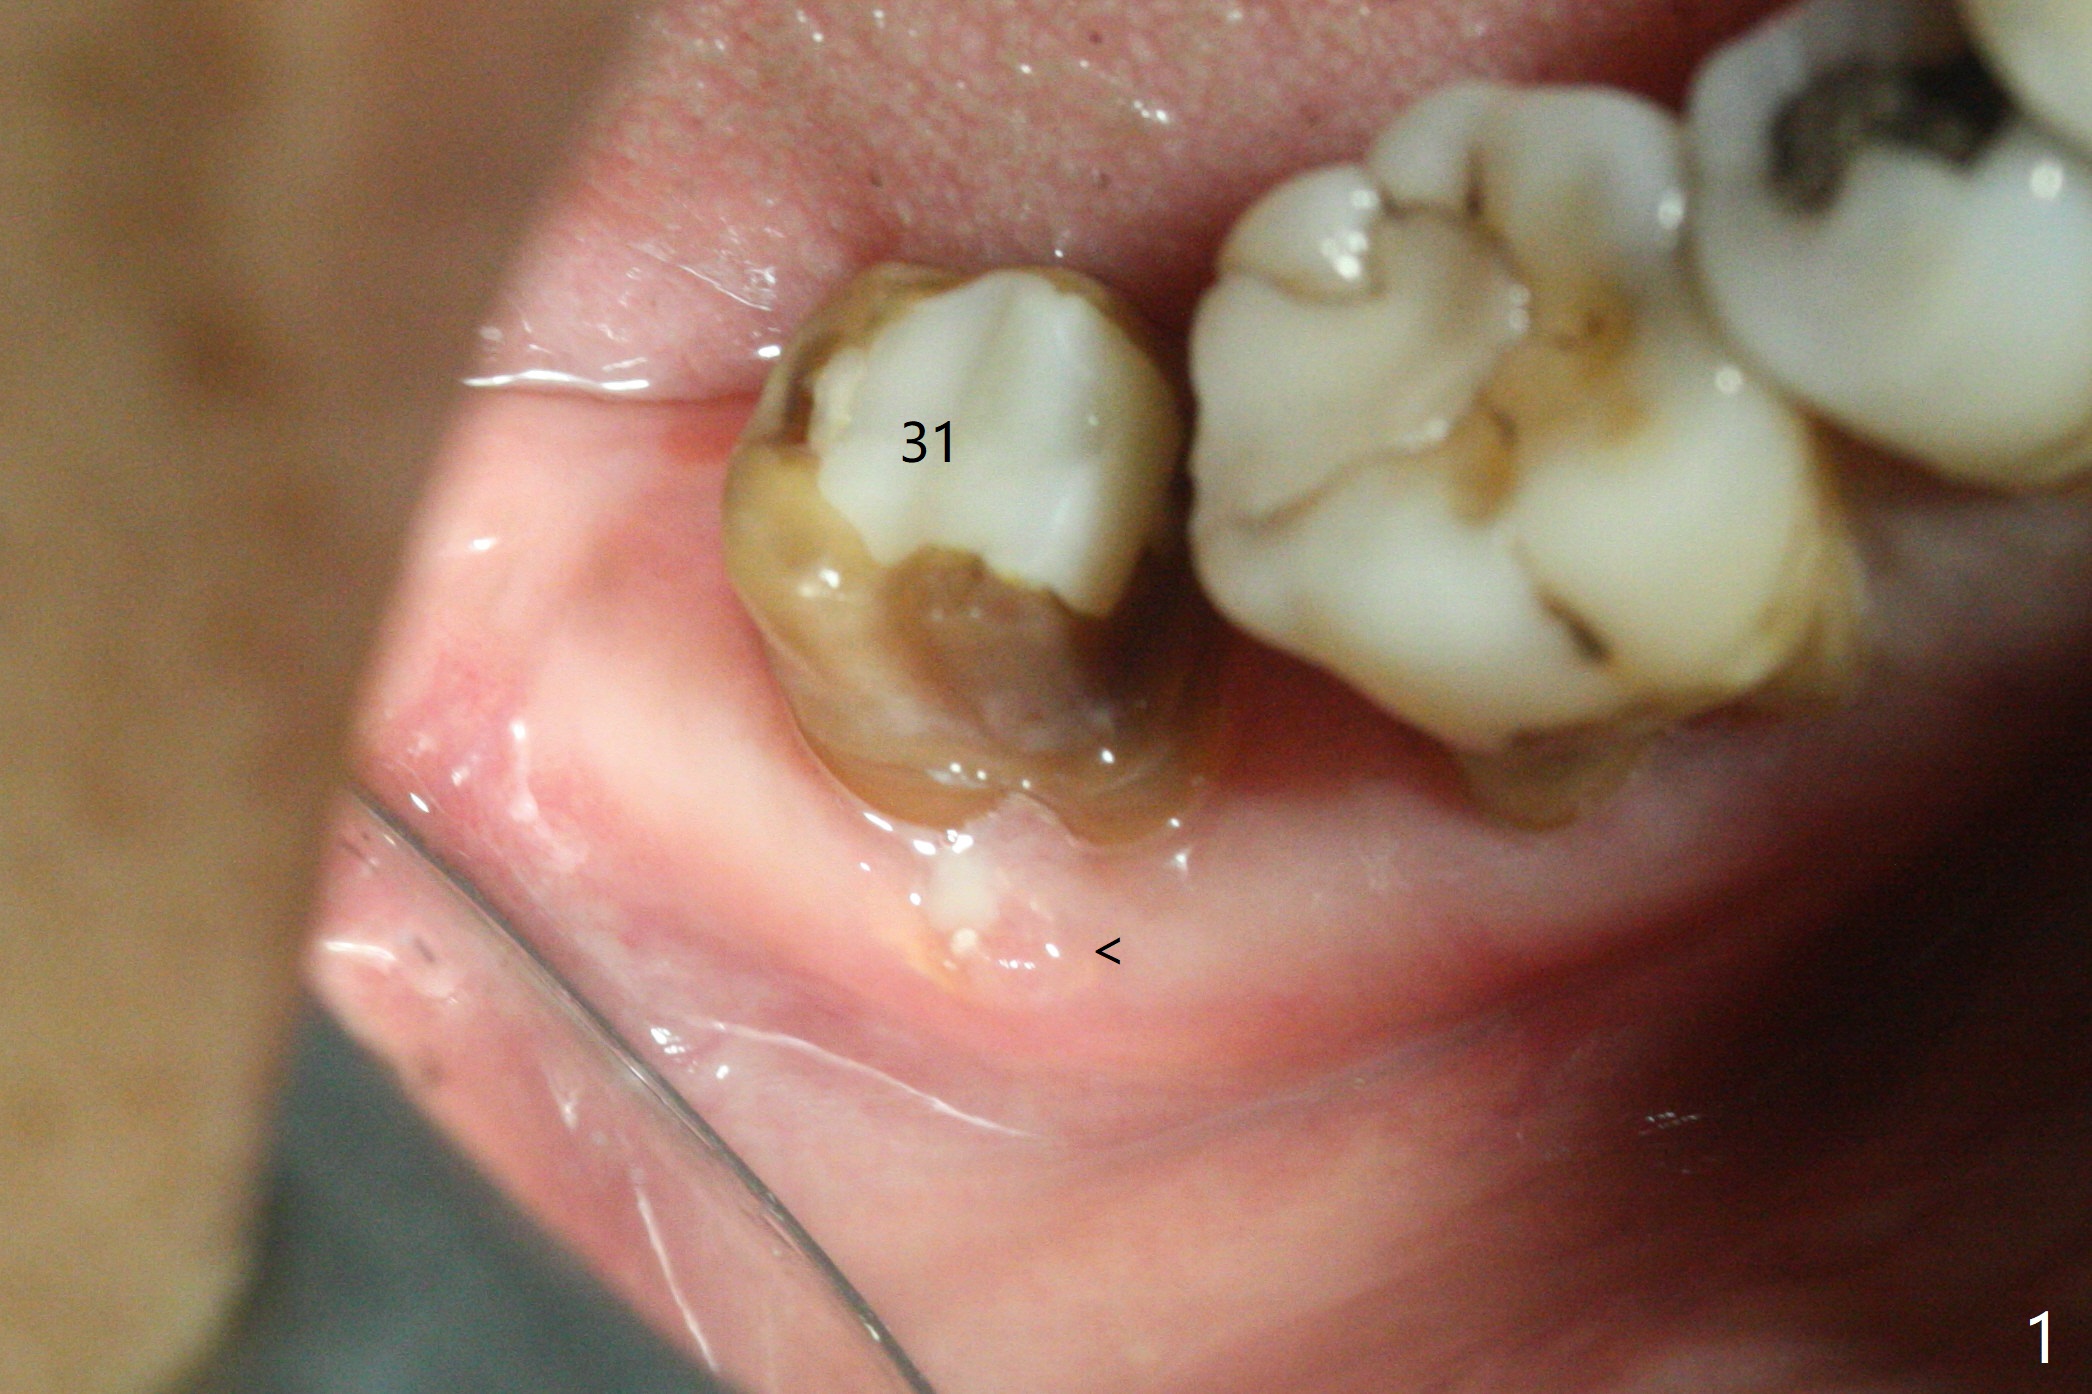

After extraction of the tooth #31 with mesial root fracture and a buccal fistula (Fig.1 <) and debride-ment, cortical: cancellous (50: 50) mineralized allograft (.5-1 mm) saturated with ~ .3 ml of .3 mg/ml of rhPDGF-BB (one component of GEM21S) is placed in the socket. Amazingly bone graft granules seem to stick to each other (semi sticky bone (Fig.2), as compared to PRF). The socket opening is covered with a piece of Osteogen plug and 12x12 mm Amnion-Chorion Allograft, followed by 4-0 PGA suture (Fig.3). The bone graft is packed as apical (Fig.4) and buccal (Fig.5 B) as possible. The patient will return to soft tissue healing check in a week. CT will be taken to determine whether the buccal plate is repaired 4 months postop. Watch Video. In fact COVIT 19 delays her return. The buccal plate seems to have reformed 7 months postop (Fig.6 >). The width and height of the ridge remains basically the same (compare Fig.7 and 8).